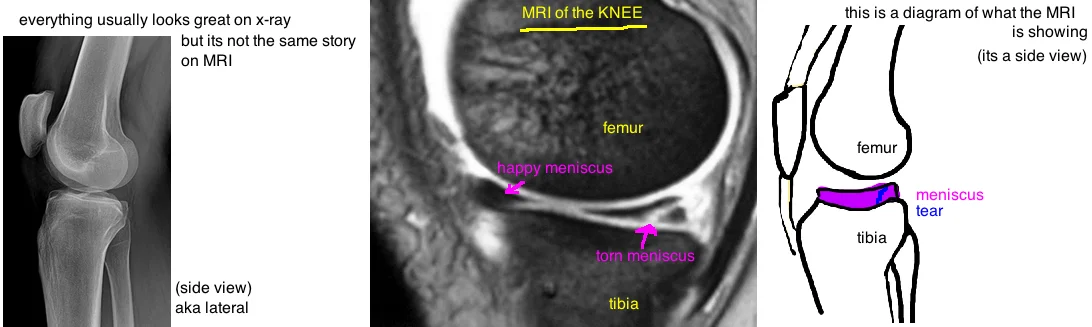

Knee Mri Torn Meniscus Pictures - Torn Meniscus Symptoms and Diagnosis - Jeffrey H. Berg, M.D. : See meniscus tear stock video clips.. These fda medical devices are made in the usa for home use. This line represents synovial fluid from the knee joint which has leaked into the torn meniscus. Magnetic resonance imaging mri knee posterior horn medial meniscus tear scantest results. How do you heal a torn meniscus without surgery? A tear in this cartilage is called a meniscal tear.

Pain, swelling, or difficulty bending the knee may be symptoms of a meniscal tear. How do you heal a torn meniscus without surgery? A doctor may use mri imaging to help diagnose a meniscal tear. Meniscus knee meniscus meniscus anatomy cartilage tears meniscus injury lateral rotation knee articular cartilage injury to the knee torn meniscus articular cartilage. This line represents synovial fluid from the knee joint which has leaked into the torn meniscus.

Tears are described by how they look and where they are located. A doctor may use mri imaging to help diagnose a meniscal tear. See full list on drrobertlaprademd.com Meniscus knee meniscus meniscus anatomy cartilage tears meniscus injury lateral rotation knee articular cartilage injury to the knee torn meniscus articular cartilage. Magnetic resonance imaging mri knee posterior horn medial meniscus tear scantest results. A tear in this cartilage is called a meniscal tear. More images for knee mri torn meniscus pictures » See full list on emedicinehealth.com

A tear in this cartilage is called a meniscal tear. Meniscus knee meniscus meniscus anatomy cartilage tears meniscus injury lateral rotation knee articular cartilage injury to the knee torn meniscus articular cartilage. The knee is the joint where the large bones of the upper leg (femur), lower leg (tibia), and kneecap (patella) meet. See meniscus tear stock video clips. In an mri, however, your doctor can even see where the tear occurred on the meniscus and how any swelling may be impacting other parts of your knee. Everyday activities like walking and climbing stairs put pressure on the knees. Robert laprade details the specifics on how to read an mri of a medial meniscus tear. There are different types of meniscus tears and a horizontal cleavage tear occurs within the fibers of the meniscus and splits the meniscus in the top and bottom pieces.

Sep 27, 2020 · if ever the meniscus is torn, an mri may reveal that its typical triangular shape will either have shifted or changed. See full list on emedicinehealth.com May 27, 2021 · an mri is a 3d picture that slices through things, and there's three planes: A tear of, or rent in, the cartilage in the knee is called a torn meniscus. What should i expect from a knee mri? To begin, we start with a sagittal view on the lateral side. See meniscus tear stock video clips. How do you heal a torn meniscus without surgery? In some cases, the torn portion will have migrated to the center of the knee joint (commonly referred to as a bucket handle tear). Meniscal tears have different names longitudinal, flap, bucket handle, torn horn, and transverse depending on where and how the cartilage tears. There are different types of meniscus tears and a horizontal cleavage tear occurs within the fibers of the meniscus and splits the meniscus in the top and bottom pieces. More images for knee mri torn meniscus pictures » Pain, swelling, or difficulty bending the knee may be symptoms of a meniscal tear.

To begin, we start with a sagittal view on the lateral side. See full list on drrobertlaprademd.com In an mri, however, your doctor can even see where the tear occurred on the meniscus and how any swelling may be impacting other parts of your knee. The coronal plane is this front plane. May 27, 2021 · an mri is a 3d picture that slices through things, and there's three planes: What are the signs of a meniscus tear? A tear in this cartilage is called a meniscal tear. A meniscal tear may occur due to squatting or twisting the knee the wrong way. This line represents synovial fluid from the knee joint which has leaked into the torn meniscus. See full list on emedicinehealth.com Severe tears or tears that cause symptoms that cannot be managed are treated with surgery and rehabilitation. How do you heal a torn meniscus without surgery? The knee is the joint where the large bones of the upper leg (femur), lower leg (tibia), and kneecap (patella) meet.